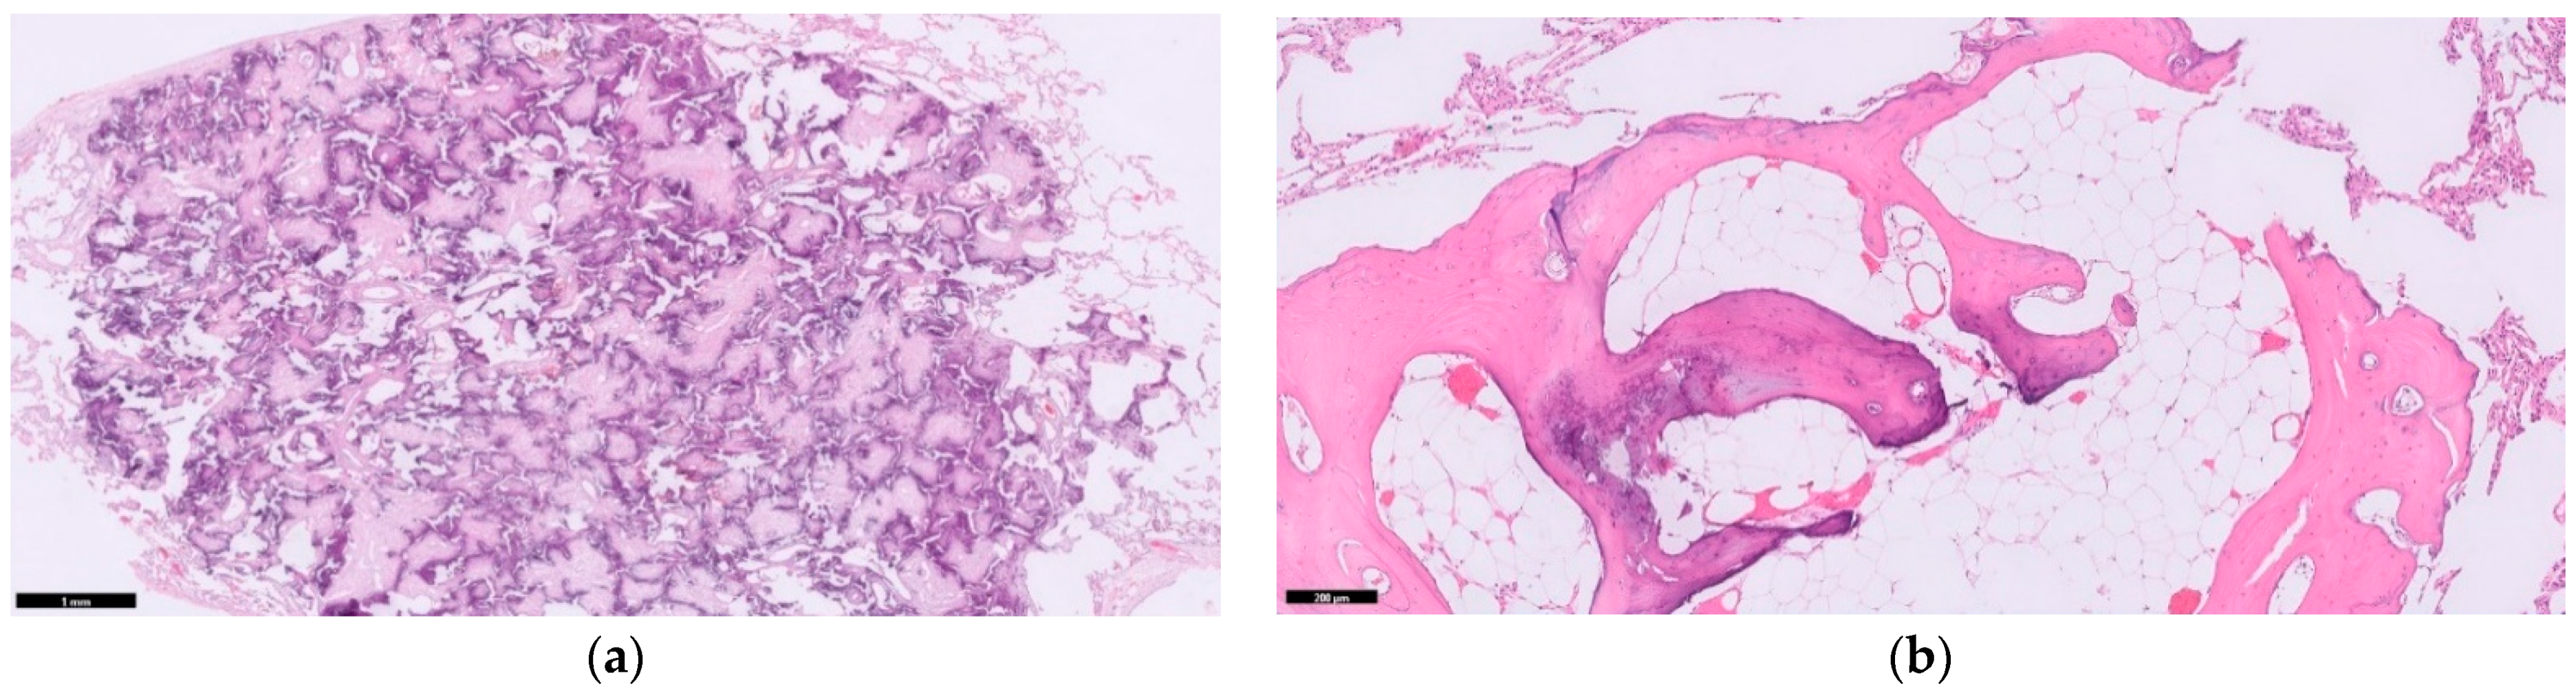

Ossification is defined as deposits of calcium in a collagen matrix in the presence of osteoblastic cells. Two distinct types of PO are distinguished in literature: nodular PO and dendriform PO. Nodular PO are secluded to the alveolar space and are often round. Dendriform PO branch through the interstitium of the septa in a tree-like coral pattern. Sometimes, the bone tissue has matured to encase osteoblasts, osteoclasts, and bone marrow with fatty cells and haematopoetic stem cell tissue (Figure 1). Even with high-resolution computed tomography, it is difficult to discern the nodular from dendriform PO. Differentiating between these two types clinically has less importance as both types may co-exist in the pulmonary tissue of the same patient [2].

Figure 1. Different forms of pulmonary ossification. (a) A rounded nodular ossification; (b) Coral-like dendriform ossification, interwoven through the alveolar septa and containing fatty marrow deposits with haematopoetic stem cell tissue (arrow). HE stain, magnification (a) 40×; (b) 100×.